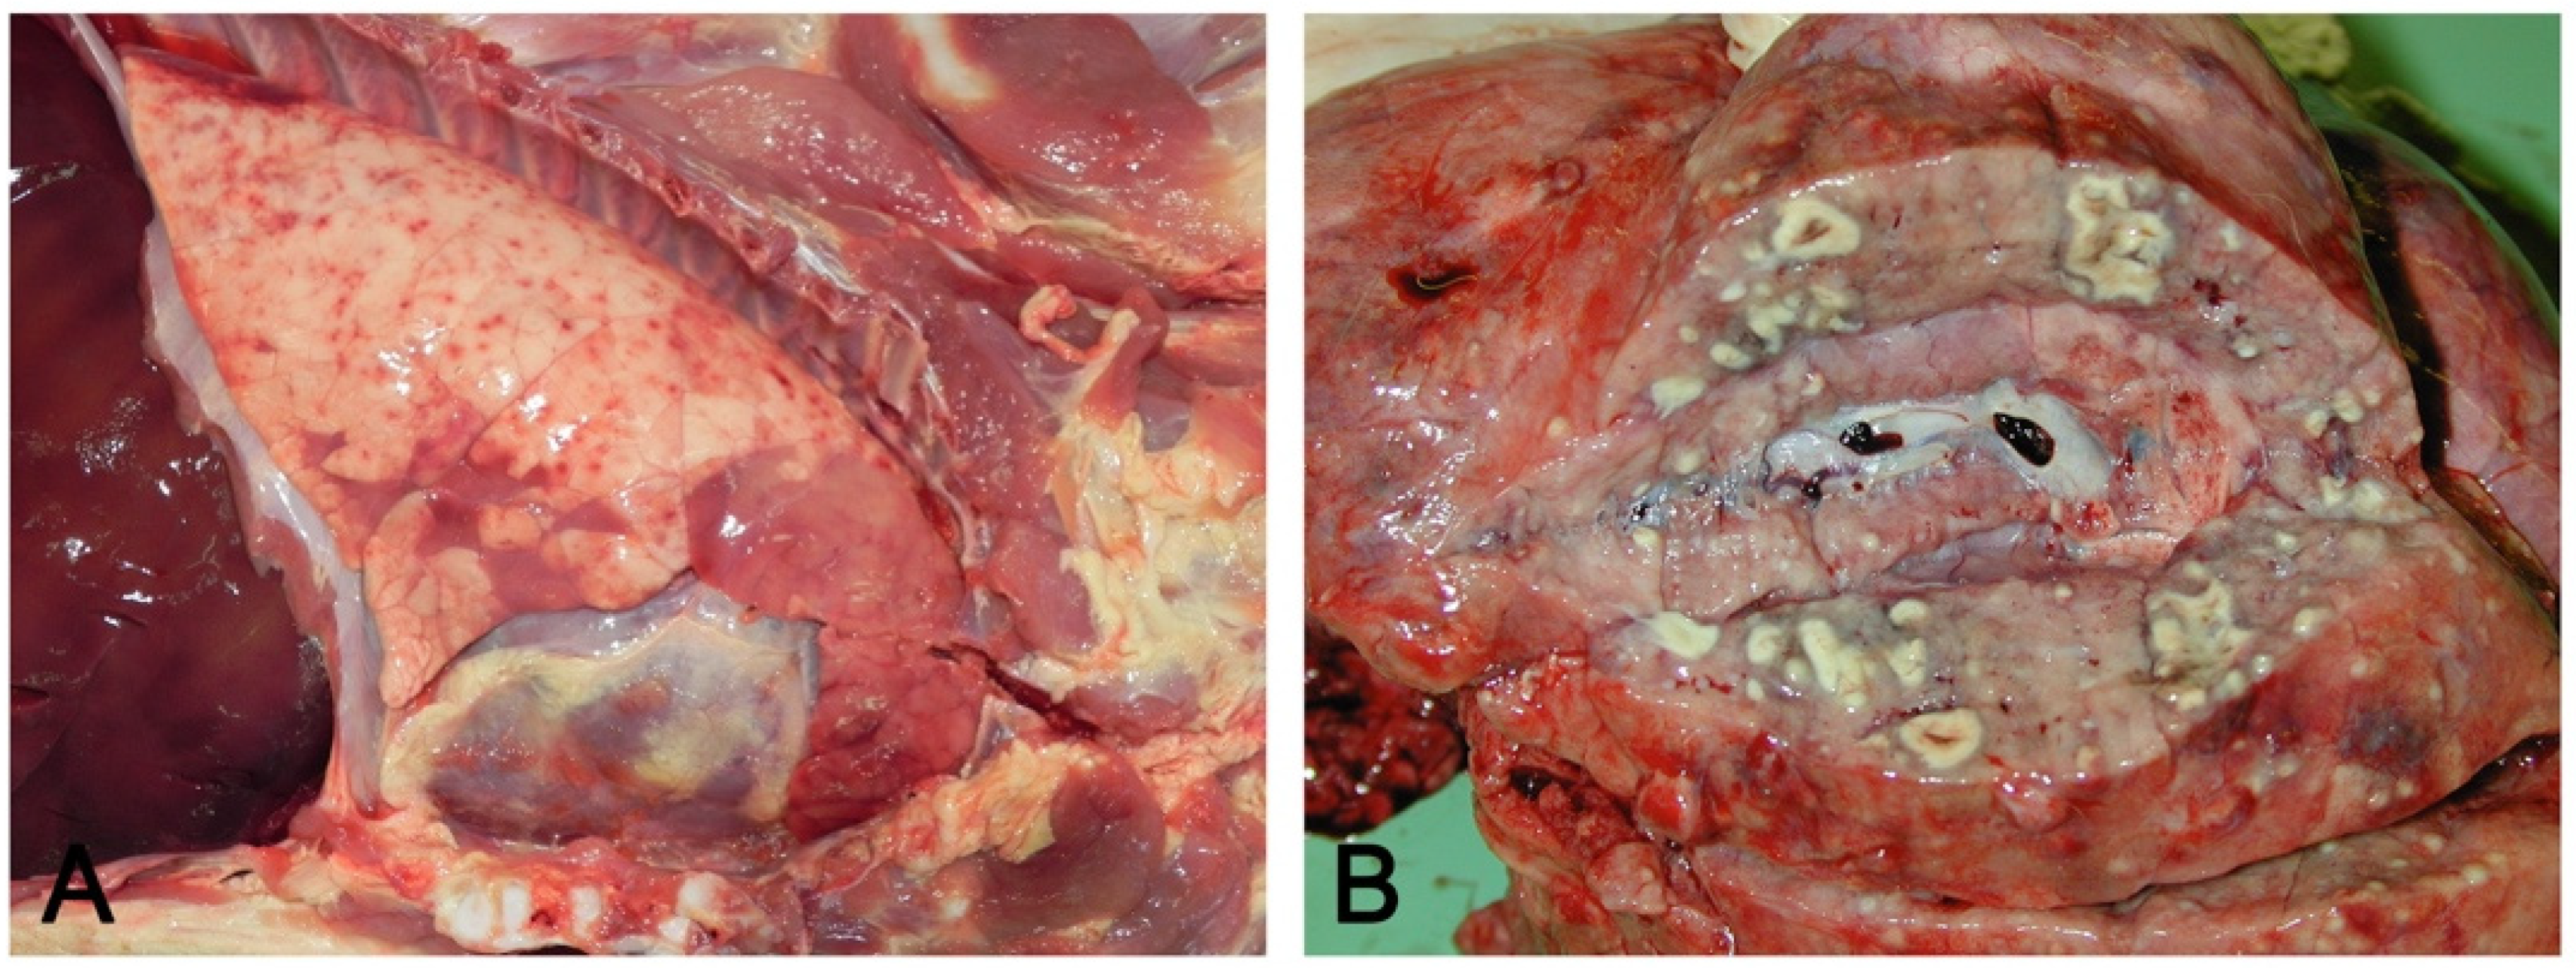

- Embolic pneumonia (arrest in the lung of septic thromboemboli originated from inflammation located elsewhere). Its prominent macroscopic feature is the presence, if recent, of randomly scattered foci of hyperemia/hemorrhage or, if chronic, of abscesses (Figure 4).

Figure 4. Hematogenous lung spread: in (A), together with a cranioventral pneumonia, the right basal lobe shows multiple acute and recent red foci of hyperemia/hemorrhage referable to bacteremia often of intestinal origin. In (B), multiple foci of suppuration surrounded by normal lung parenchyma, due to lung arrest of microthrombi originating from septic phlebitis outside the lungs. - Interstitial pneumonia (arrival of pneumotropic or endotheliotropic agents from primary sites of replication through the blood circulation as in PRRSV and PCV2 infections and septicemia from Gram-negative bacteria). The macroscopic appearance is an interstitial pneumonia characterized by lungs that fail to collapse, with rib impressions, patchy, lobular or diffuse distributions of color variation (ranging from red in the acute stages to a pale whitish color in the chronic forms), changes in consistency (firm texture), interstitial edema (in acute stage), and missing airway involvement (Figure 5).